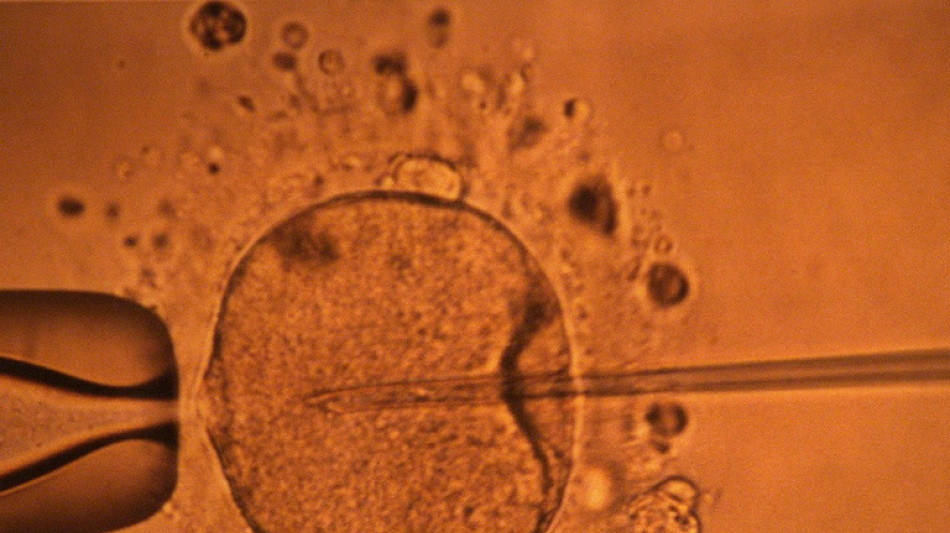

La concentración de espermatozoides, uno de los factores de la fertilidad masculina, disminuyó significativamente en todo el planeta en las últimas décadas, según un estudio publicado el martes.

"La concentración de espermatozoides disminuyó significativamente entre 1973 y 2018", resumen los autores de este trabajo publicado en la revista Human Reproduction Update y realizado mediante la compilación de unos 40 estudios previos.